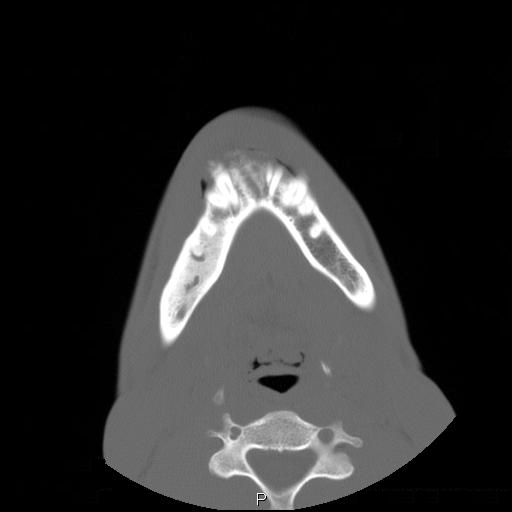

Clinical information The patient was a 23 year-old man who went to see the dentist because of dull pain, swelling of the chin,  and loosened lower front teeth. He was referred to this hospital after initial examination. A CT scan was performed and and a biopsy was taken. Representative images are presented here. Panel D is a sagittal reconstruction from axial CT scans. A resection was subsequently performed.

A. B. C. D.

CT scan: On the CT scan images (Panel A, B, C, and D), two lesions are present.  There is a lesion at the mental protuberance that appears to have penetrated the cortex and invaded into the soft tissue. The patchy hyperdensity strongly suggests that this lesion has mineralize elements ( in Panel B). The border of the lesions in the mandible is poorly defined. The penetration of the bone and extension into the soft tissue is best appreciated in the sagittal reconstruction in (Panel D). These features are highly suggestive of a malignant neoplasm that originates from the bone with extension into surrounding soft tissue. The hyperdensity of the mass suggests bone formation and the radiologic features are suggestive of an osteosarcoma. In the right body of the mandible, there is a diffusely expansile lesion  with some hazy hyerdensity (Ú in Panel B). The cortical bone overlying this lesion is intact. This lesion may represent extension of the osteosarcoma into the body. However, it may also represent a co-existing fibrous dysplasia.